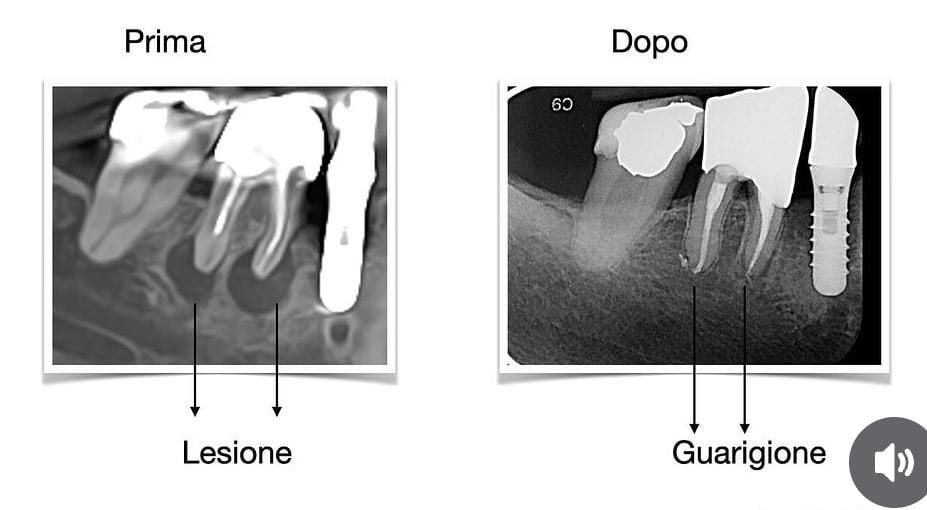

- Diagnosi Precisa: Una diagnosi accurata è il primo passo cruciale. Presso il nostro studio dentistico, utilizziamo moderne tecniche di imaging, come la radiografia digitale, per esaminare attentamente l’area coinvolta e identificare la presenza di granulomi apicali. La tc cone beam rappresenta un’indagine radiologica 3D ad alta definizione che consente di individuare granulomi anche laddove le tradizionali rx endorali dovessero fallire.

- Trattamenti Conservativi: In molti casi, i granulomi apicali possono essere trattati con successo attraverso il trattamento endodontico o terapia canalare. Questa procedura prevede la rimozione dell’otturazione precedente, la pulizia del sistema canalare e la sigillatura accurata per eliminare l’infezione. Il ritrattamento rappresenta sempre la prima scelta e l’utilizzo del microscopio operatorio risulta fondamentale per garantire un risultato ottimale e minimamente invasivo.

- Monitoraggio Post-Trattamento: Dopo qualsiasi procedura, è fondamentale monitorare attentamente il progresso e garantire il successo del trattamento. Ulteriori follow-up e radiografie periodiche ci consentono di assicurarci che il granuloma si risolva completamente.